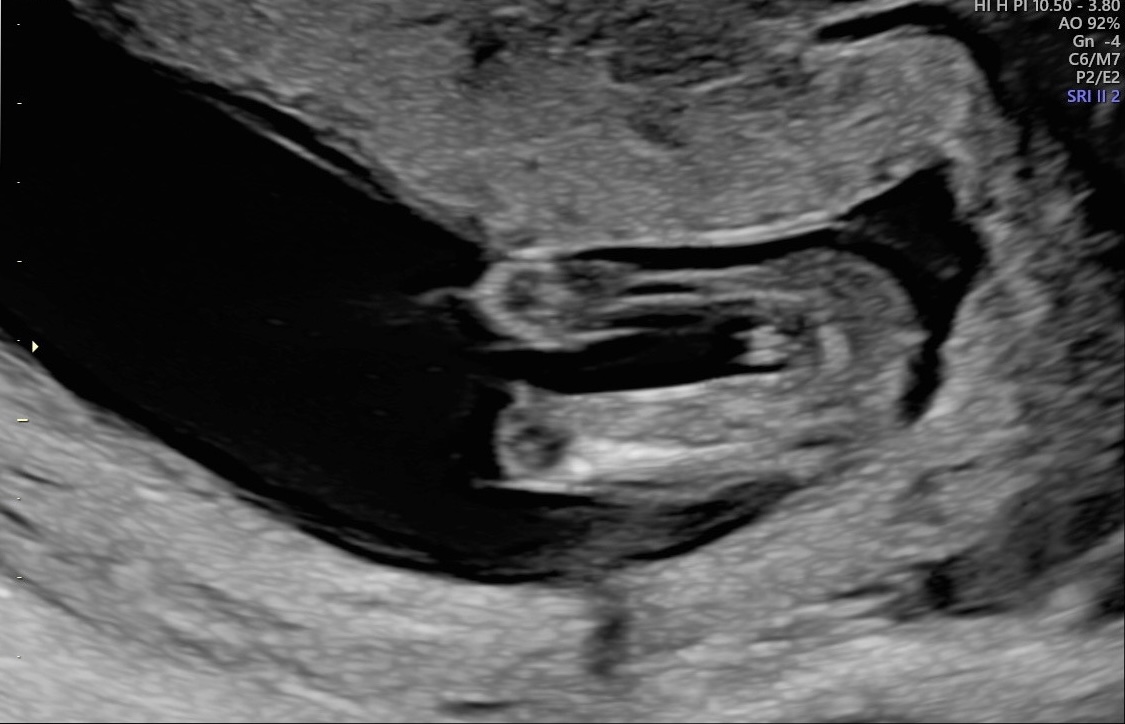

Here is a side shot! Also 13w+5d or 14+0 weeks.

What do you think??

I'd definitely lean girl - especially with the nub being that direction on the second pic! ;)

I'd say girl. The nub especially looks very girly.